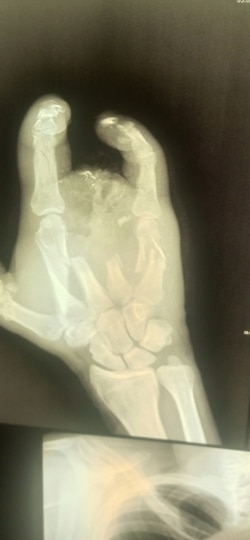

Рука Алексея после ранения на войне

Оказалось, что с незажившими ранами покалеченного солдата отправили в гражданское медучредждение для того, чтобы на руках у него не было документов из военного госпиталя. И сейчас Алексей не может доказать, что стал калекой в бою.

– Как меня вытащили, как везли до полевого госпиталя – не помню ни черта. Очнулся, узнал, что получил осколочное ранение, обжег шею, глаз, невзрывное осколочное ранение оторвало мне полруки, снесло все пальцы, разгромило всю кисть. Увезли меня в Луганск, там позволили три недели полежать, и все. Выпнули из военного госпиталя в обычную больницу. Я еще удивился, зачем на последние пять дней. Потом узнал.